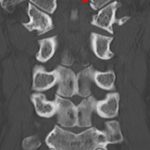

- Acute minimally displaced fracture of the left occipital condyle

- Possible acute nondisplaced fracture of the right occipital condyle

Acute minimally displaced fracture of the left occipital condyle.

Possible acute nondisplaced fracture of the right occipital condyle.